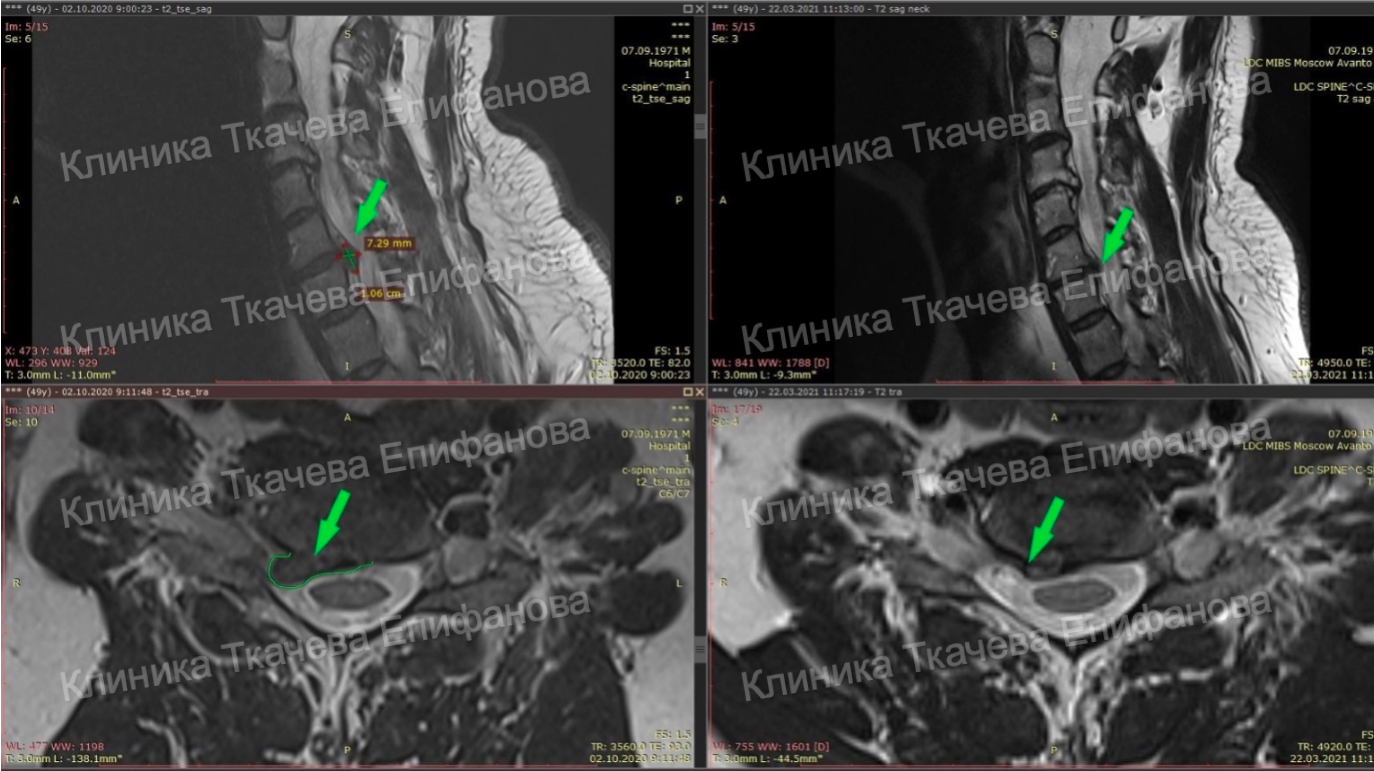

Удаление грыжи шейного отдела отзывы